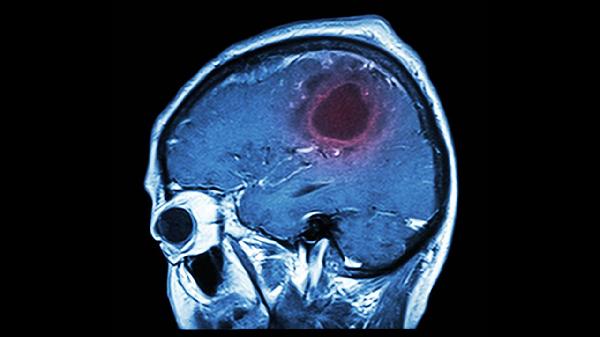

脑血栓的治疗药物主要有阿司匹林肠溶片、硫酸氢氯吡格雷片、阿托伐他汀钙片、依达拉奉注射液、丁苯酞软胶囊等。脑血栓通常由动脉粥样硬化、心房颤动、高血压、糖尿病、高脂血症等原因引起,表现为偏瘫、言语障碍、头晕等症状。建议及时就医,积极配合医生治疗,在医生的指导下服用合适的药物,并做好饮食调理。